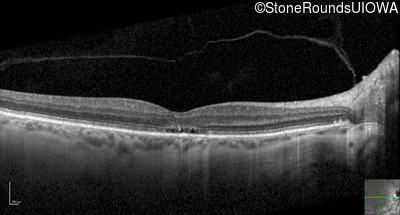

Optical Coherence Tomography - Right - 20/100

Exemplar / OCT Stack

OCT Stack